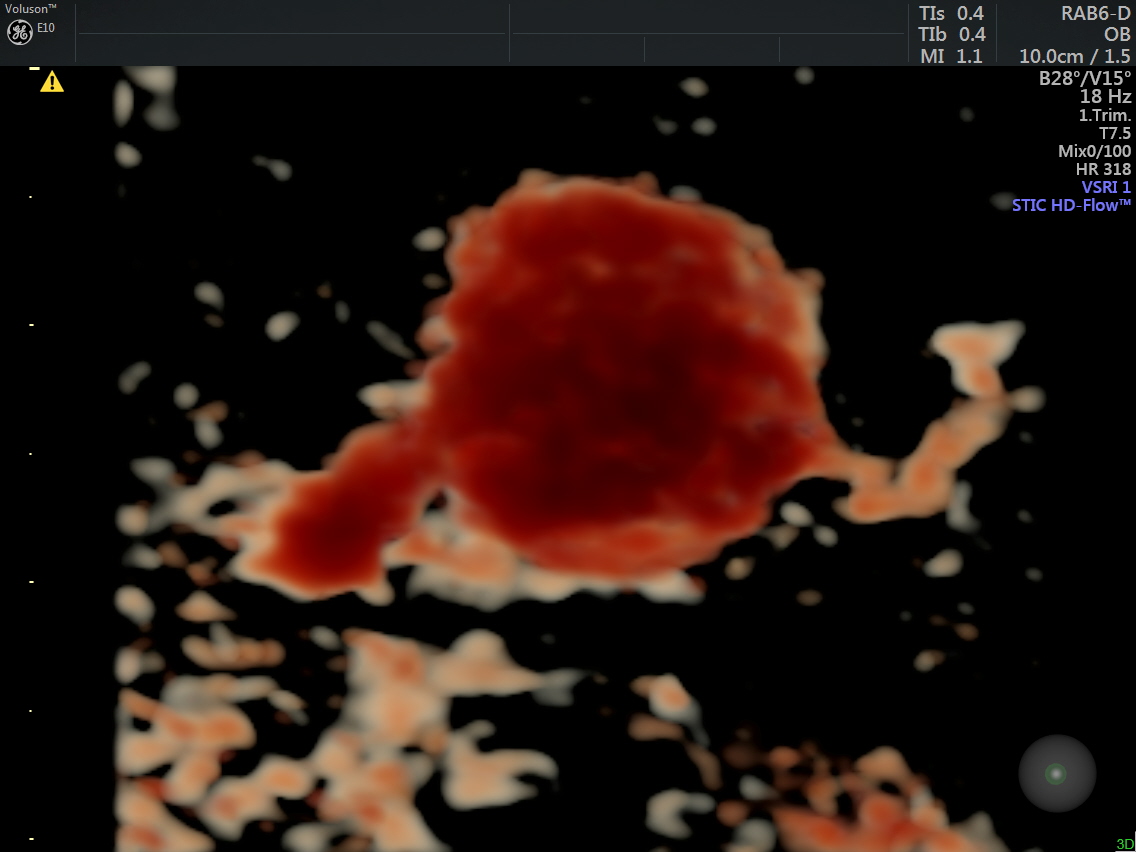

A prominent globular vascular structure of size 1.71 + 1.28 cms was seen in the right lobe.

The red globular structure seen in colour flow was striking.

A small feeding vessel leading from the portal vein entering the vascular structure is seen.

The venous flow is established by power doppler in the following pictures.